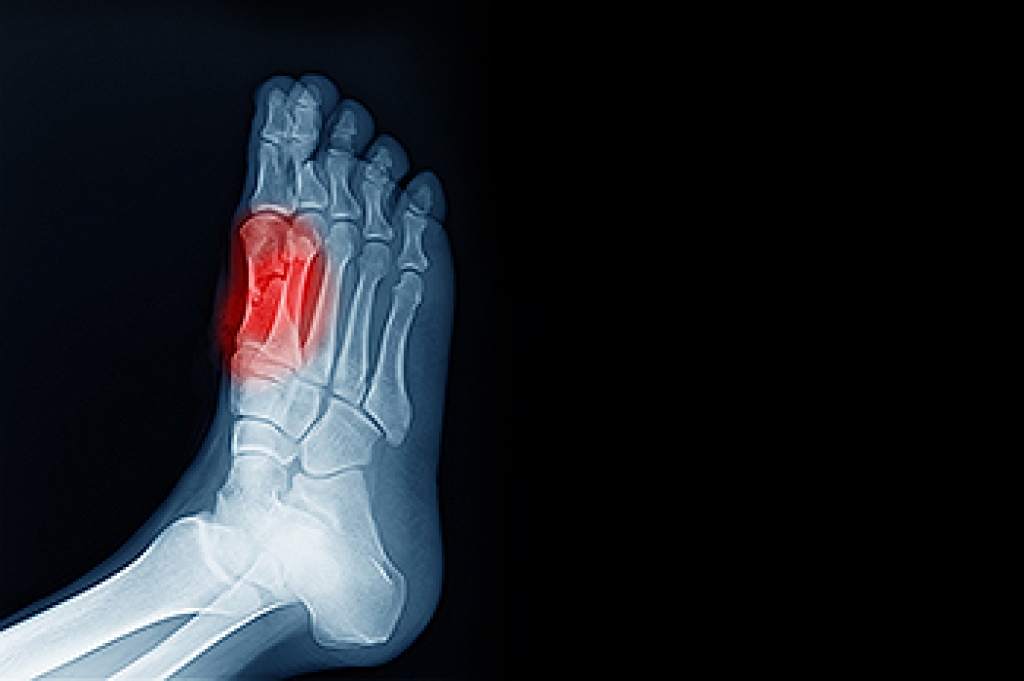

- Pain around the heel or arch area

- Swelling around the inside of the ankle

If you are experiencing pain and stress on the foot you may weaken the posterior tibial tendon, which runs around the inside of the ankle.